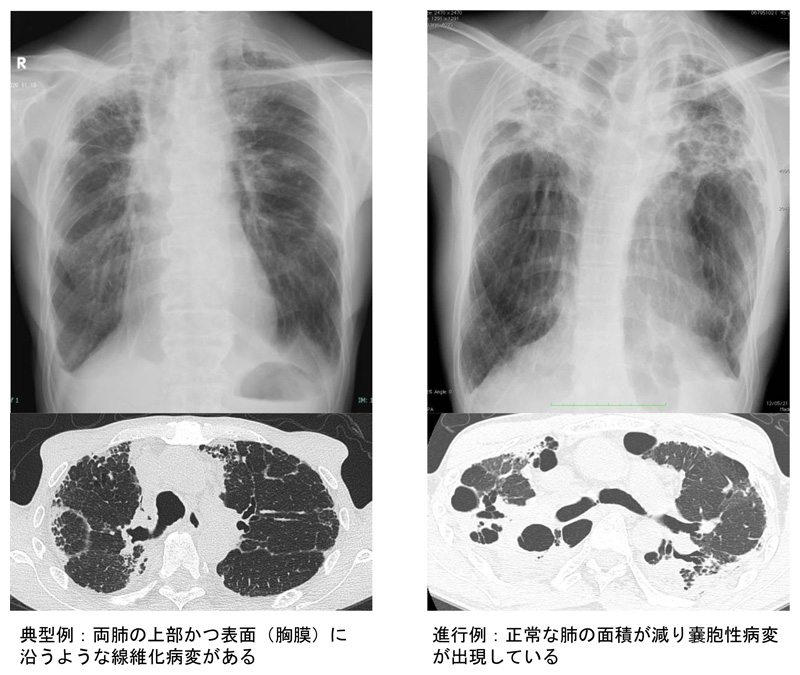

胸のレントゲンでは両肺の上部に帯状の影が見え、進行すると肺上部が縮みます。CTでは上の肺が白く硬く見え、時に気管支の拡張や小さな空洞のような変化(嚢胞)を伴います。呼吸機能検査では肺の容量が減ると同時に、息を吐いても肺に残ってしまう空気(残気)が多くなるのが特徴です。これらの所見を組み合わせて診断します。